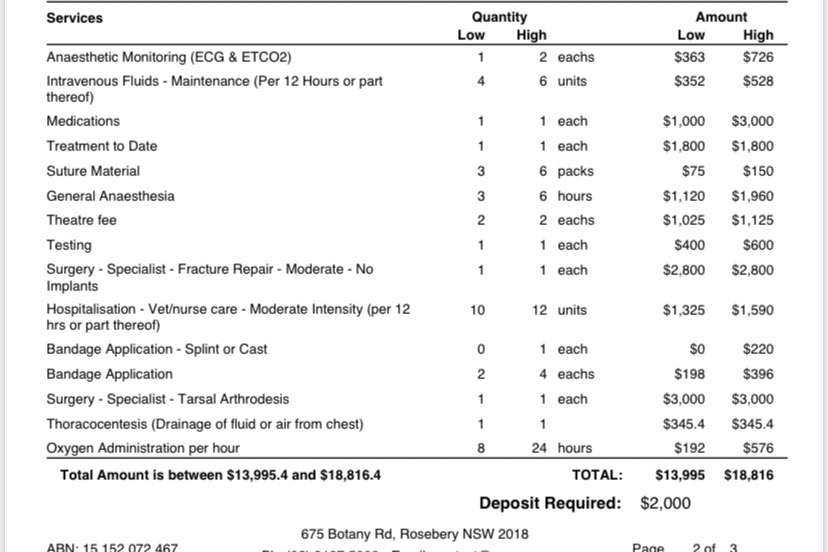

The surgeons at Sydney Vet Emergency & Specialists have said that the full cost of care and surgery will be about $15k-$20k. This amount is significant but at the same time pales in comparison to the possibility of losing an integral part of our family.

P.S For transparency, below is an estimate of costs for the medical procedures they sent to my boyfriend.